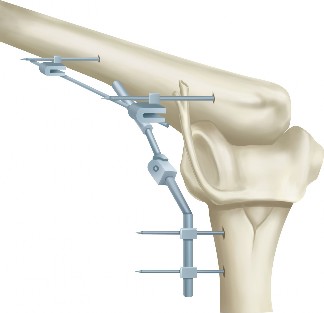

The correct answer is (C). The dorsal scapular artery and nerve travel beneath the rhomboid minor and major muscles approximately 1 to 2 cm medial to the medial scapular border. Portal placement should therefore be located approximately 3 cm medial to the medial scapular border (Fig. 2–80).

Figure 2–80_Reproduced with permission from Warth, RJ, Spiegl UJ, Millet PJ. Scapulothoracic bursitis and snapping scapula syndrome: a critical review of current evidence. _Am J Sports Med 2014 Mar 24. [Epub ahead of print]

Answer A is incorrect because the long thoracic nerve is rarely endangered unless dissection is carried lateral. The suprascapular nerve can be endangered if a portal is placed superior to the scapular spine. The deep branch of the transverse cervical artery becomes the dorsal scapular artery. The spinal accessory nerve travels with the superficial branch of the transverse cervical artery, and its branches are at risk if a portal is placed superior to the scapular spine. Scapulothoracic bursitis is usually managed nonoperatively. Nonoperative treatment includes activity modification, NSAIDs, PT, and corticosteroid injections. If symptoms are recalcitrant to conservative management or associated with an osseous or soft tissue mass, surgical intervention is indicated. Arthroscopic, open, or a combined operative approach can be performed. Arthroscopy is more technically demanding, but it does not require postoperative immobilization because the rhomboids and levator scapulae are not transected and reattached to the scapula after partial scapula resection is performed.